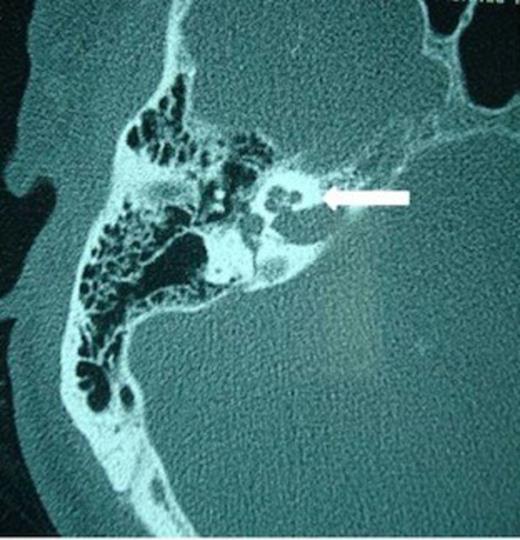

When surgery was attempted, cochleostomy revealed complete obliteration of the scala tympani. Efforts to insert the electrode through the scala vestibuli were also unsuccessful. The procedure was abandoned and a subsequent high resolution CT scan showed complete ossification of the left cochlea and but a patent cochlea on the right (Fig. 3 and 4). Twenty days following the initial attempt, a right cochlear implantation was successfully performed. Following mapping, programming, and aural rehabilitation, the patient was able to understand speech and use the telephone.